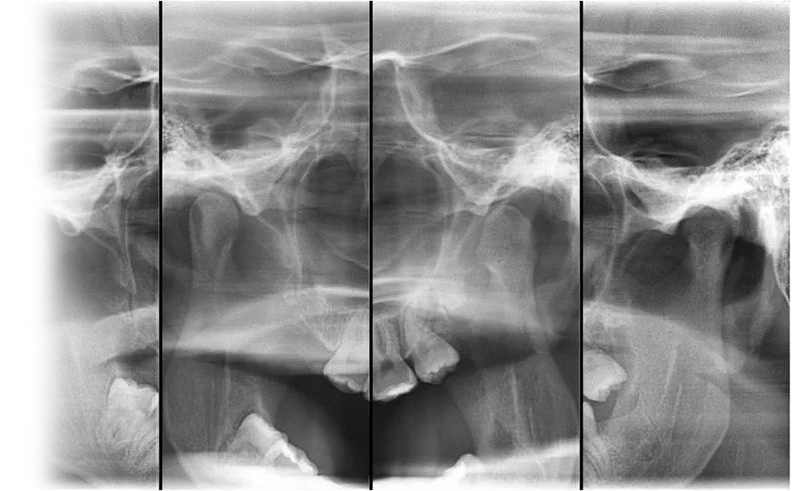

Рентгенография височно-нижнечелюстного сустава – важный метод прицельного исследования височно-нижнечелюстных суставов.

Рентген выполняется в двух проекциях.

Показания для проведения рентгена височно-нижнечелюстного сустава:

• болевые ощущения при движении челюстью;

• «щелчки» в суставах;

• «заклинивание» челюсти;

• для исключения дегенеративно-дистрофических, костно-травматических изменений в суставе;

• для исключения патологии суставного диска рекомендовано проведение МРТ височно-нижнечелюстного сустава